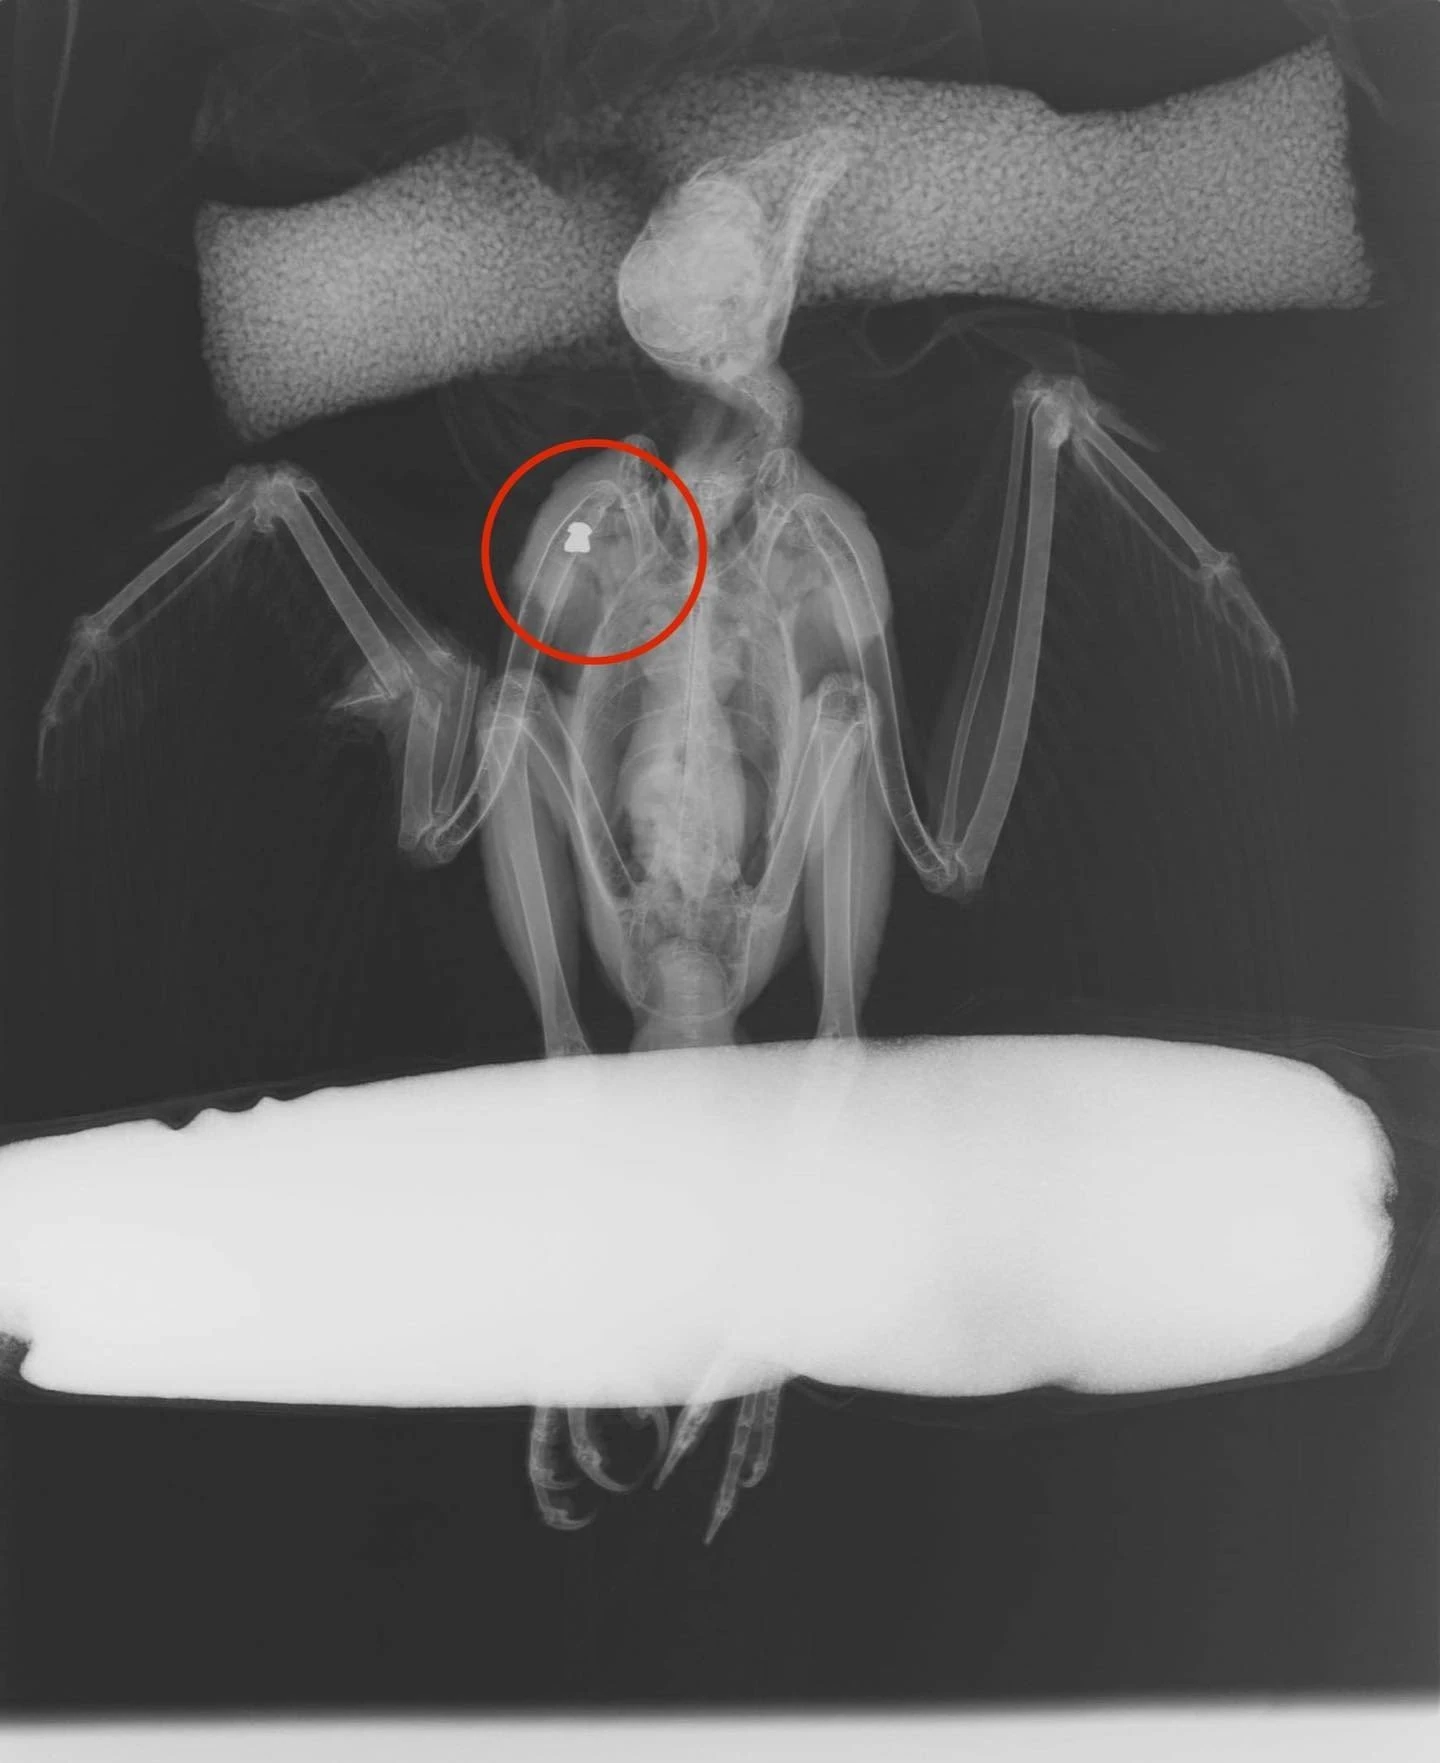

Εντοπίστηκε τραυματισμένη από αεροβόλο όπλο, με πολύ σοβαρό κάταγμα στο αντιβράχιο

Τραυματισμένη από αεροβόλο όπλο, με πολύ σοβαρό κάταγμα στο αντιβράχιο, βρέθηκε μια γερακίνα στη Θεσσαλονίκη.

Μετά από προσπάθειες αφαιρέθηκε το σκάγι και έγινε ανάταξη του κατάγματος, αλλά χωρίς καλή πρόγνωση.